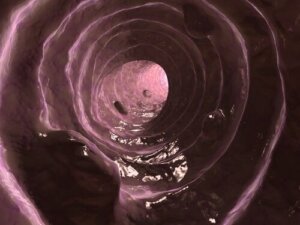

Mukus, işlevi kolon astarını kaygan ve nemli tutmak olan – solunum epitelinin ürettiğine benzer şekilde – bağırsak mukozası tarafından salgılanan bir maddedir.